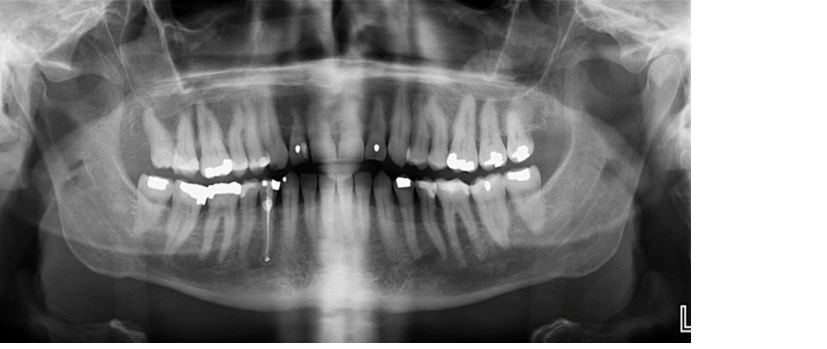

”Smala incisiver”

- Står för långt fram i panoramamaskinen/längre från röntgen fokus/närmare detektorn.

- Incisiverna ser smala ut.

”Breda incisiver”

- Står för långt bak i panoramamaskinen/närmare röntgenfocus/längre från detektorn.

- Incisiverna ser breda ut.

”Ena sidan bredare än den andra”

Patientens högra sida kommer längre från detektorn/närmare focus och tvärtom på vänster sida. Höger sida avbildas då bredare än vad den är och vänster sida ser smalare ut.

Höger sida får mer överlappningar.

”Rörelse”

Patienten har rört sig under exponeringen vilket ger en vågigt suddig bild som exemplet ovan.